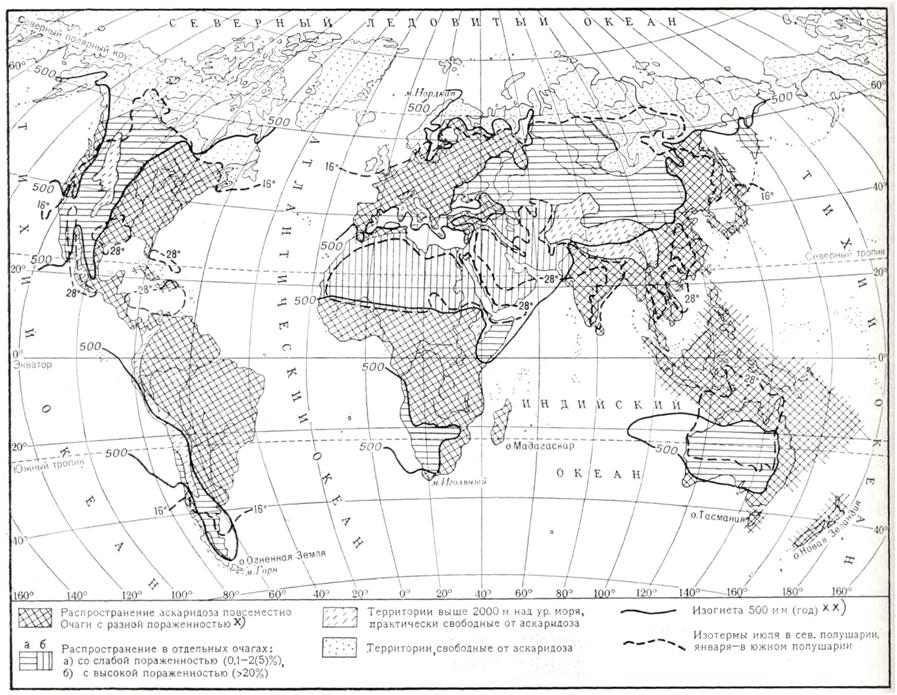

АскаридозАскаридоз (ascaridosis; греческое askaris, askaridos + - osis) — гельминтоз, вызываемый круглыми червями — аскаридами. У человека могут паразитировать несколько видов аскарид, из которых все, кроме Ascaris lumbricoides, являются облигатными паразитами животных и у человека в половозрелой стадии встречаются крайне редко. ЭтиологияВозбудитель — Ascaris lumbricoides — крупные раздельнополые гельминты (рис. 1). Размер самок 25—40 см, самцов —15—25 см. Головной конец снабжен тремя большими кутикулярными губами, окружающими ротовое отверстие. Хвостовой конец самки прямой с коническим придатком, самца — загнут на брюшную сторону. Яйца овальные (рис. 2), снабжены пятью оболочками, наружная из них толстая, фестончатая (белковой природы), прокрашивается пигментом фекалий в коричневый цвет. Встречаются яйца и без белковой оболочки. За белковой располагается трехслойная глянцевитая оболочка. Обе оболочки предохраняют зародышевую массу от механических повреждений. Внутренняя (тонкая) оболочка — липидная, полупроницаемая, задерживает соли и органические вещества, но проницаема для воды. Размер яиц 0,050-0,070 × 0,040— 0,050 мм. Аскариды могут продуцировать и так называемые неоплодотворенные яйца (яйцеклетки), имеющие неправильную форму, крупные размеры (0,050 — 0,106 × 0,040 — 0,050 мм) и лишенные зародышевой массы. Взрослые аскариды обитают в тонком отделе кишечника, где удерживаются, согнувшись дугой или свернувшись кольцом, упираясь в стенки кишки. Питаются пищевой кашицей, находящейся в кишечнике, и поверхностными слоями слизистой оболочки тонкой кишки. Самки после оплодотворения выделяют яйца на стадии одного бластомера, все развитие которых происходит в окружающей среде. Скорость развития зависит от условий температуры, влажности и состава почвы. Яйцо становится заразным после того, как сформировавшаяся в нем личинка совершит линьку и превратится в инвазионную личинку в чехлике.

Рис. 2. | ||